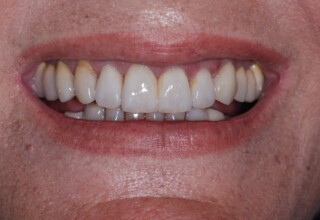

Όψεις Πορσελάνης

Οι όψεις πορσελάνης είναι ο καλύτερος τρόπος αντιμετώπισης αισθητικών προβλημάτων στην πρόσθια περιοχή του στόματος. Συνδυάζουν συντηρητική αφαίρεση οδοντικής ουσίας και πολύ υψηλή αισθητική απόδοση. Στο παρακάτω εκτεταμένο περιστατικό υπήρχαν: παλαιά σφραγίσματα, δυσχρωμίες, κακό σχήμα και μήκος δοντιών, κακή αναλογία δοντιών-ούλων. Έγινε προσεκτικός εργαστηριακός σχεδιασμός σε εκμαγεία απ’όπου προέκυψαν προσωρινές όψεις που τοποθετήθηκαν στο στόμα για δοκιμή και διορθώσεις. Όταν οριστικοποιήθηκαν οι μετατροπές, οι προσωρινές χρησιμοποιήθηκαν σαν οδηγός για τις μόνιμες. Οι πέντε μόνιμες όψεις πορσελάνης που κατασκευάστηκαν για τα πέντε πρόσθια δόντια της άνω απεκατέστησαν σχεδόν άψογα την αισθητική εμφάνιση της ασθενούς.

Αρχική εμφάνιση

Τελική εμφάνιση